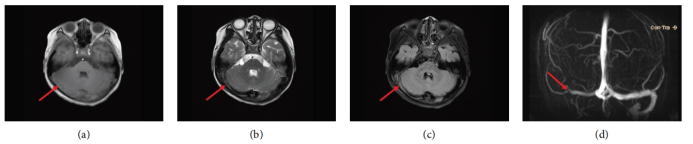

· 诊断性MRI/MRV:入院后进行的MRI/MRV检查明确显示了右侧横窦、乙状窦及颈内静脉颅内段的血栓形成,表现为T1WI呈混杂信号,T2WI及FLAIR序列呈高信号,MRV上相应区域出现血流信号中断(充盈缺损)。

治疗后7天

MRV

右侧横窦、乙状窦血栓负荷显著减少,可见部分血流信号恢复。

治疗有效

治疗后3个月

MRI/MRV

右侧横窦、乙状窦及颈内静脉颅内段血栓完全消失,静脉窦完全再通,血流信号恢复正常。

血栓完全溶解